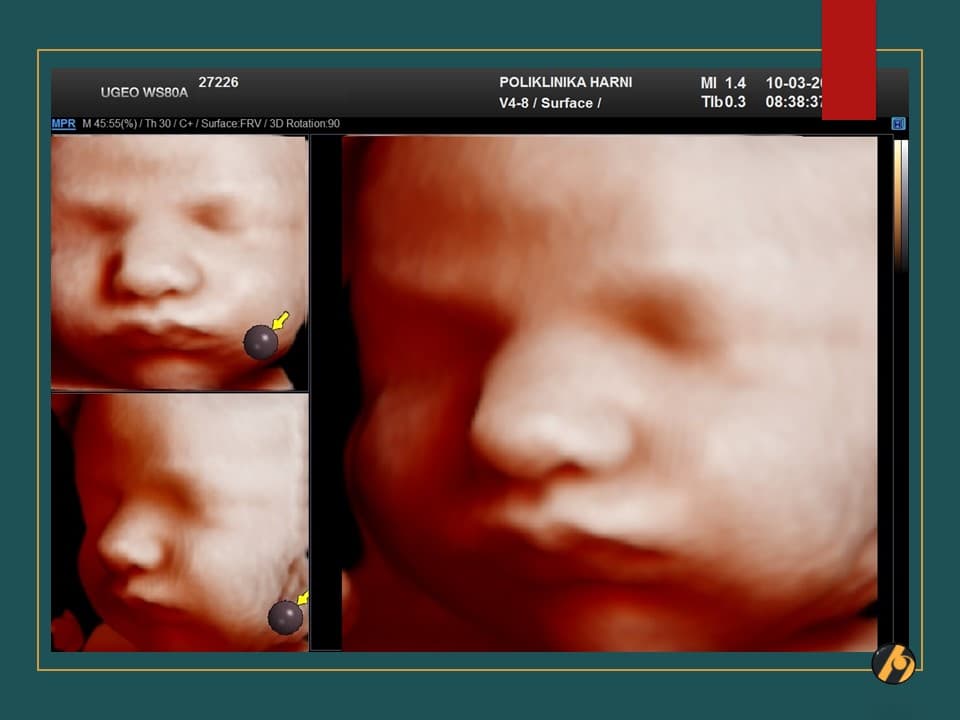

S 37. tjednom trudnoće Vaša beba postaje klinički zrela i potpuno spremna za porod. S ovim tjednom se također završava razdoblje mogućeg preranog poroda.

U sljedećim danima beba će i dalje dobivati na težini, pri čemu se ovaj dobitak osobito odnosi na odlaganje masnog tkiva. U ovo vrijeme beba odlaže u prosjeku 14 g masti/dan. Esencijalne masne kiseline ulaze i u sastav mijelina, specijaliziranog omotača moždanih i kičmenih živaca čime započinje i konačni proces dozrijevanja živčanog sustava. Ovaj proces mijelinizacije nastaviti će se i nakon bebinog rođenja.

Vaša beba dugačka je oko 47 cm, i teška 2,750 – 2,950 g.